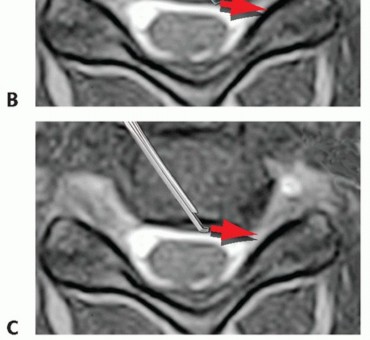

### TECH FIG 2 • Caspar pin placement. Because greater preparation of the inferior endplate on the cephalad vertebra is necessary, the surgeon should place the upper Caspar pin (C5) further away from the endplate (eg, in the midbody of C5 or more cephalad) while being cognizant of not entering the adjacent disc space above. The Caspar pins are placed in the midline to avoid compromising later screw fixation during plating. To achieve parallel distraction, the pins should be placed parallel to the disc space. If the tips (ie, the leading ends) converge, relative kyphosis of the disc space occurs with placement of the Caspar pin spreader and distraction; if the tips diverge, relative segmental lordosis occurs with placement of the Caspar pin spreader and distraction. It may be desirable at times to try to increase lordosis through this mechanism. This generally requires greater preparation of the inferior endplate of the cephalad level versus the superior endplate of the inferior level. It is important not to remove too much bone off the inferior endplate of the cephalad level, however, as doing so limits the bone available in the vertebra to accommodate a plate and screws. This is particularly the case in smaller patients who have smaller vertebrae. A high-speed burr is helpful in decorticating the endplates. The creation of a parallel rectangular space within the disc space allows insertion of a graft appropriately sized to match the larger height present at the center of the disc space. Both endplates should be thoroughly denuded of cartilage and decorticated to reveal bleeding bony surfaces to enhance the chance of successful fusion.5 Alternating use of the high-speed burr, curettes, and the pituitary rongeur will allow the surgeon to reach the posterior disc space and the PLL. During ACDF, we are more aggressive with endplate preparation than during corpectomy because ACDF grafts tend to be more stable than corpectomy grafts. If major endplate resection is performed during corpectomy, significant settling or pistoning of the graft may occur (see Chap. SP-7), which is less likely with ACDFs. Furthermore, in cases of extensive spondylosis, wide disc space preparation facilitates decompression along the floor of the canal in ACDF surgery. When performing corpectomy, on the other hand, the additional room is not usually necessary because removing the vertebral body creates wide access for work at the disc level. ### Anterior Foraminotomy The discectomy is performed to the level of the PLL, with complete removal of the posterior annulus. It is safer to leave the PLL intact during the initial foraminotomy or resection of posterior osteophytes when the burr is being used because it acts as a protective layer to the neural elements. Once the bony removal is complete, the PLL can then be resected.2 The medial half of the posterior uncinate is thinned under direct visualization with a high-speed burr to unroof the entry zone of the foramen (TECH FIG 3). The microscope is angled appropriately to visualize the uncinate. In general, it is easier to decompress the contralateral rather than the ipsilateral foramen, although decompression of both is certainly possible. Thus, in cases of unilateral radiculopathy, we prefer to approach the spine from the side opposite to the patient's symptoms. It is important not to force a large instrument into a severely narrowed foramen if it does not fit easily. Instead, the surgeon 5 should use the burr to thin the uncus until the instrument can easily be passed into the foramen.

TECH FIG 3 • Anterior foraminotomy. A. The burr is used to thin down bone in the lateral aspect of the canal (arrow) until only a thin shell is left. The PLL is left intact as a protective layer to the neural elements until burring is completed. B. A curette is used to outline the bony edges and ensure that they are thin enough for passage of a curette or Kerrison rongeur. The PLL does not necessarily need to be resected during foraminotomy if the pathology is due solely to uncinate bone spurs, although we routinely do so and do not consider the decompression complete until the lateral edge of the dura and the exiting root are clearly visualized and palpated to be free of compression. C. A 2-mm Kerrison is then used to remove bone spurs. It is critical to hug the posterior margin of the uncinate during this move to avoid injuring the root underneath, which exits the canal ventrolaterally at about 45-degree angle. Note also that the vertebral artery is typically at the level of the mid-disc space. Thus, it is important to stay posterior when removing osteophytes off of the uncus rather than straying anteriorly where the vertebral artery is at greater risk. Constant irrigation is performed to prevent thermal injury and to clear away bone debris. If visualization is adequate, continued thinning of the osteophyte can progress until only a thin shell of bone is left. A microcurette or 2-mm Kerrison is then used to resect the thinned osteophytes. Alternating between microcurettes or a Kerrison and the burr, the foramen can be gently and progressively carved out laterally. The nerve root exits the spinal canal at roughly 45-degree angle ventrolaterally. Thus, it is imperative to avoid blindly placing a burr, curette, or Kerrison deep to the uncinate to avoid root injury. Instead, one should closely hug the uncinate while entering and decompressing the foramen (see FIG 1). Foraminotomy is complete when a micro nerve hook or curette can easily be passed into the foramen anterior to the exiting root without resistance.6 ### When and How to Resect the Posterior Longitudinal Ligament With soft disc herniations, a defect in the PLL is often present through which the nuclear material extrudes (TECH FIG 4A,B).